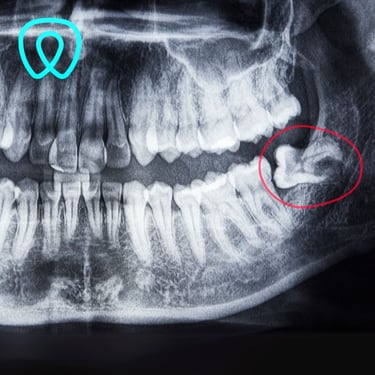

Contamos con todas las especialidades dentales: ortodoncia, implantes, cirugía, endodoncia, periodoncia, odontopediatría, odontología cosmética, prótesis dental.

Servicios Dentales

Atención integral en odontología para todas las edades y especialidades con enfoque en la prevención.